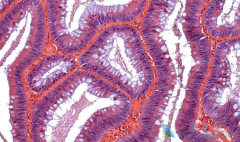

• 简述西妥昔单抗的适应症及抗肿瘤机制

简述西妥昔单抗的适应症及抗肿瘤机制

EGFR单克隆抗体—西妥昔单抗( cetuximab )作用于表皮生长因子受体(EFGR)的单克隆抗体西妥昔单抗是目前研究最为广泛的靶向药物之一,其疗效在多种肿瘤治疗中得到肯定。目前在全球范围内爱必妥获批的适应症有:转移性头颈部癌,非转移性头颈部癌,转移 ...